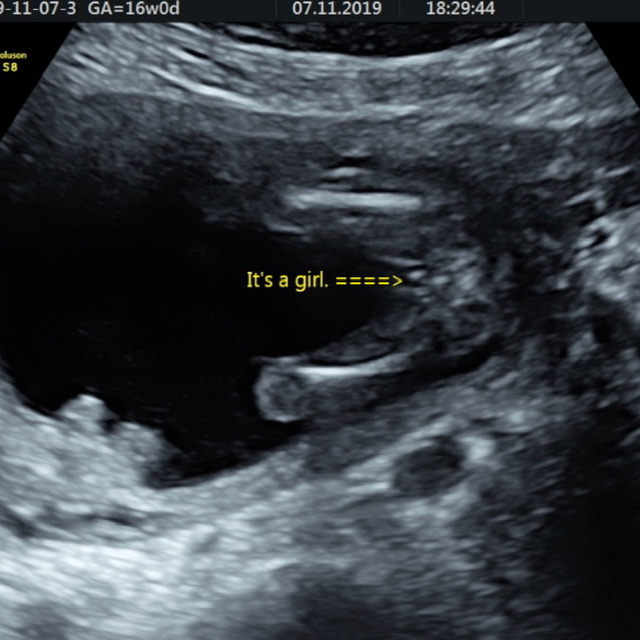

Is this definitely a girl? 16 week potty shot

Attachment 42082

Hi all, so I have 2 boys, got all early girl nub shot guesses and at 16 weeks have been told by the sonographer it is a little girl. I’ve been and bought some baby girl clothes and was very excited, until someone said to me my potty shot looks like a boy. My two boys came to the scan and are over the moon about having a little sister as of course am I. Please can someone shed some light? I don’t want to go for the next month thinking (and buying) girl only to be told boy at the next scan.

Please help ladies x